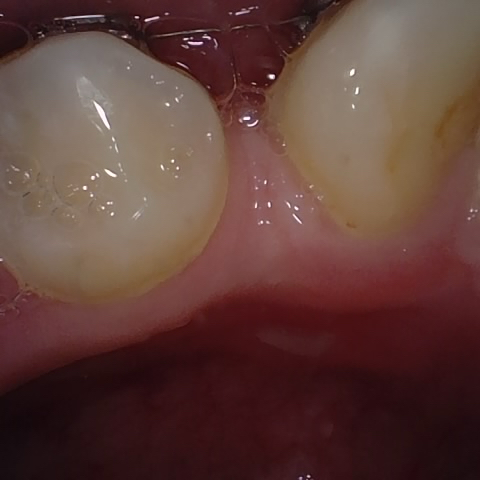

Annotated as "Bad"